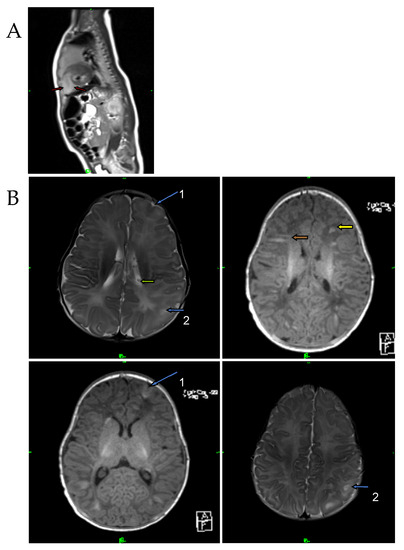

A 34-year-old pregnant woman was referred for examination at the Department of Obstetrics and Gynecology in her 30th week of gestation. The pregnancy was uncomplicated, and fetal parameters, including the abdominal circumference, femur length, and biparietal diameter, were consistent with the gestation age. An abnormal cardiac ultrasound scan of the fetus initiated a fetal echocardiography with a GE Voluson E8 high-end ultrasound system (GE Healthcare, Chicago, IL, USA). Left ventricular expansion was interpreted as a rhabdomyoma (31 × 32 × 33 mm), and some smaller tumors (multiplex tumors) were detected (Figure 1A). The fetal cardiac rhythm was a sinus without arrhythmia. In addition, echo-dense formations (cortical tubers and subependymal nodules) were also described in the brain tissue using fetal magnetic resonance imaging (FMRI), including T2-weighted imaging obtained using HASTE IRM (Siemens Healthcare GmbH, Erlangen, Germany) (Figure 1B).

Figure 1. T2-weighted MRI image of the fetus at the 30th week of gestation. (A) Red arrows show cardiac rhabdomyoma (31 × 32 × 33 mm). (B) Blue arrows show cortical tubers, and green arrows represent subependymal nodules in the brain.